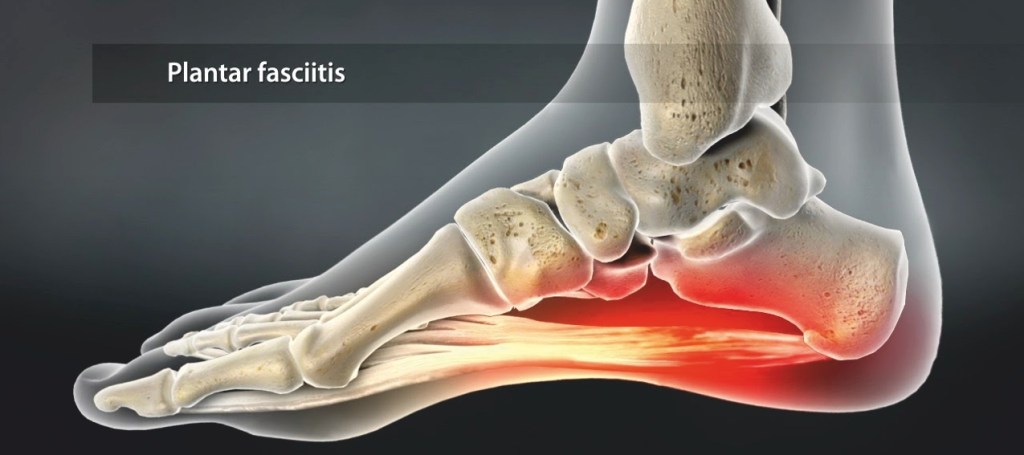

Правильная работа опорно-двигательного аппарата — одно из обязательных условий высокого качества жизни на всем ее протяжении.